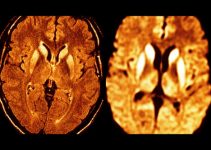

- Компьютерная томография.

- Магнитно-резонансная томография.